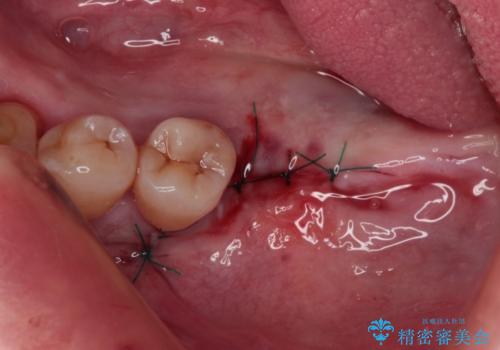

- インプラント治療を前提に下顎の部分矯正を始めたものの、そのまま長い間放置しているとのことで来院された患者様です。

全体的に歯肉が腫れており、歯周病により抜歯をしなければならない歯がある状態でした。

矯正治療を仕上げ、必要に応じて歯周外科処置を行い、適宜インプラントを埋入しながら咬み合わせを回復させていくこととしました。

治療前は磨き残しが多く見られ、全体的に歯肉が腫れている状態でしたが、抜歯の必要な歯を抜いたことで口腔内の環境が改善され、磨き残しも少なくなってきました。